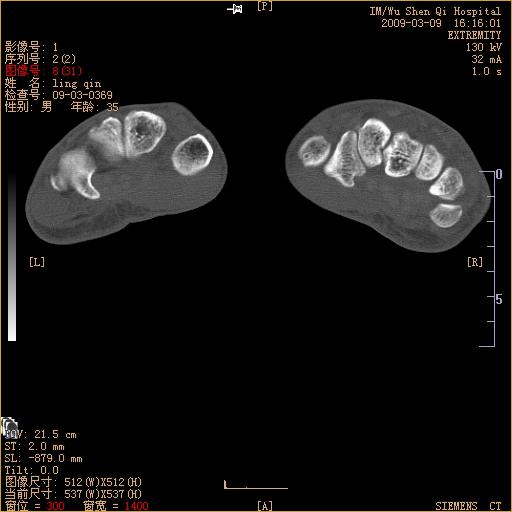

标题: CT18570:右手外伤10余天 [打印本页]

标题: CT18570:右手外伤10余天

请上传x线平片。舟状骨骨折可能大。

请上传x线平片,腕骨多骨骨折

舟状骨骨折。

左侧舟骨及桡骨茎突骨折,第一掌骨基底部好像也有骨折,建议上传平片